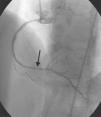

A 64-year-old white woman with a history of hypertension was admitted to hospital with new-onset chest pain consistent with angina. She had had multiple coronary angiograms (CA) four years previously for repeated episodes of typical chest pain and admissions. The CA showed non-obstructive coronary artery disease in the range of 40–50% in the left circumflex artery (LCx) which was confirmed to be non-obstructive by fractional flow reserve during the angiogram; no catheter-induced vasospasm occurred during the CA. Because of continued episodes of chest pain, she was taken off metoprolol and started on diltiazem 240mg once a day for possible vasospastic angina. She was then asymptomatic for the following four years, and also had a dobutamine stress echocardiogram, which was negative, about two months before the present admission for screening due to disease identified on her last CA. At this admission, she had new symmetrical anterolateral and inferior T inversion on the ECG consistent with ischemia; troponin levels were minimally elevated (0.3ng/ml). The patient had been seen by her primary care physician three days previously for a routine follow-up and was taken off diltiazem and started on nebivolol 10mg/day in addition to her medications of HCTZ 25mg and lisinopril 40mg/day, Lipitor 40mg, and enteric-coated aspirin 325mg/day for blood pressure (BP) control. In hospital she was started on nitro paste and intravenous (IV) heparin and her home medications continued. Because of continued chest pain in hospital and mildly elevated troponin I levels, she was scheduled for CA. She experienced chest pain at the beginning of the coronary angiogram, which initially revealed a 70% lesion and slow flow in the mid left anterior descending artery (LAD), a 90% lesion in the mid LCx and a 99% lesion in the ostium of the second obtuse marginal (OM2) (Figure 1, black arrow). The right coronary artery (RCA) had a distal 80–90% stenosis (Figure 2, black arrow). During preparation for percutaneous intervention in the LCx and OM2, intracoronary (IC) nitroglycerin was given for vessel sizing, after which there was resolution of the lesions in the LAD and decrease in the mid left LCx lesion to 50–60%, and resolution of the OM2 lesion, suggestive of significant reversible coronary artery spasm (Figures 3 and 4, white arrows). IC nitroglycerin was also administered in the RCA, in which lesion resolution was also seen. The coronary intervention was aborted, the patient's chest pain was resolved after IC nitroglycerin and she was started on IV nitroglycerin in the interim. Nebivolol was discontinued; diltiazem started in post-catheterization orders. She continued to have occasional episodes of chest pain for about 24hours after discontinuation of nebivolol. She was weaned from IV nitroglycerin the next day and started on oral isosorbide mononitrate. The following day the ECG changes resolved with no more episodes of chest pain; she was discharged home and was event-free in follow-up.